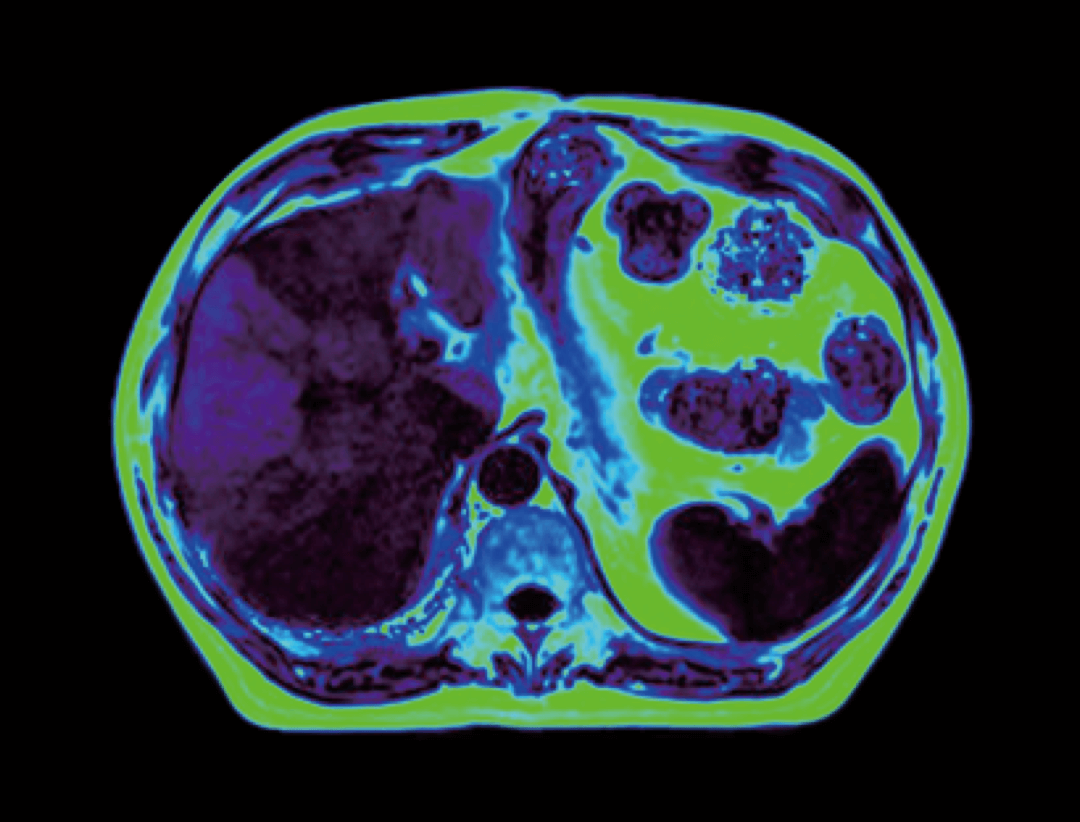

Dzięki opracowanej przez UIH technologii korekty uMR®580 cechuje się doskonałą jednorodnością pola magnetycznego.

Inteligentna technologia kompensacji prądów wirowych zapewnia wysokie parametry gradientów uMR®580.